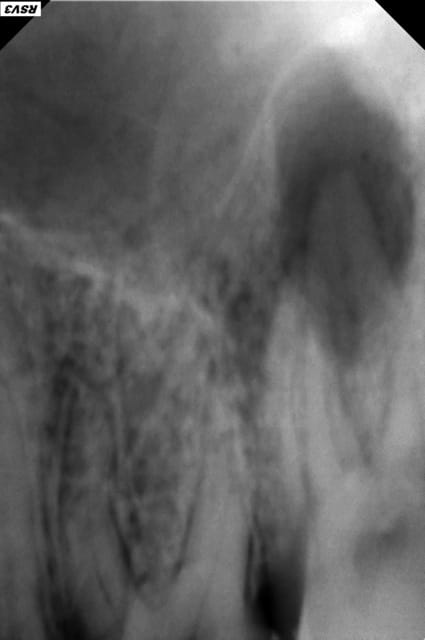

Patiente 18 ans, se présente pour douleurs à la pression dans le secteur 2.

Examen clinique: Fistule palatine et voussure vestibulaire en regard de 27.

Douleur percussion 27.

La dent est indemne. Pas de carie.

La radio parle d'elle même.

C'est bien une nécrose pulpaire qui s'est compliqué en abcès apical? C'est possible sur une 7 une nécrose spontanée comme ça (j'entend par la un choc antérieur ou autre...)